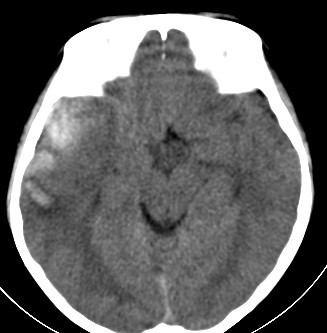

外伤一天,m,21y,骨窗示右颞骨骨折.

请大家看看,是脑内还是脑外(硬膜下还是硬膜外).请说说理由.谢谢.

右侧颞叶大片状形态不规则高密度影,边缘较模糊,无明显白质挤压移位。支持脑错裂伤、脑内血肿。

右侧颞叶大片状形态不规则高密度影,内缘较模糊,外缘紧贴颅板,无明显白质挤压移位伤。

依据:1.右侧颞叶不规则形血肿密度影,周围有水肿;

2.有明显占位效应;

3.颅板下硬膜下间隙存在。

脑内脑外全有,上方比较局限近似梭形改变,考虑硬膜外血肿。没有跨过颅缝,且是脑膜中动脉所在的位置。中线移位,占位效应明显。后方条带状增高影,周围有水肿带,考虑脑内血肿。

右颞叶见混杂密度灶(以高密度灶为主)右侧脑室受压变形,中线结构左移,右颞部颅骨内板下见弧形高密度灶,右侧裂池及部分脑沟内见高密度灶;

结论:1:右颞叶脑挫裂伤;

2:右侧硬膜下血肿;

3:蛛网膜下腔出血。